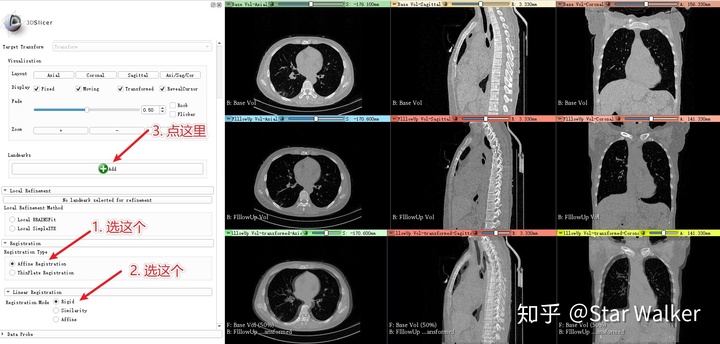

添加标志点之前,建议先按照下图进行操作,尤其是先按照下图中的第一步和第二步,选择参数设置。第一步和第二步的基本想法是,先从一个最基础的、也是最好调整、不容易出错的空间变形方式开始,先把两套数据基本对齐了,再切换到更复杂、更精准的空间变形方式上,取得更好的配准效果。关于选项1和2的具体含义,咱们后面再细说。

- 相信我,一定要先做上图中的第一步和第二步。不然,下面的步骤添加标志点时,很容易找不到标志点。

- 添加每个标志点之前,都需要先点击上图箭头3指向的“Add"按钮。也就是点一下按钮,在图像中点击一下鼠标左键,添加一对标志点。

- 基本满意后,可以依次尝试在“Linear Registration"子面板中,选择”Similarity“和Affine“,看看能否取得更好的效果。也就是,切换到更复杂、自由度更大的变形方式,看看效果如何。

- 上面都是在“Registration Type"为”Affine Registration"的前提下,来操作的。如果感觉效果已经差不多了,可以切换到“Registration Type"中的”ThinPlate Registration“再试试。